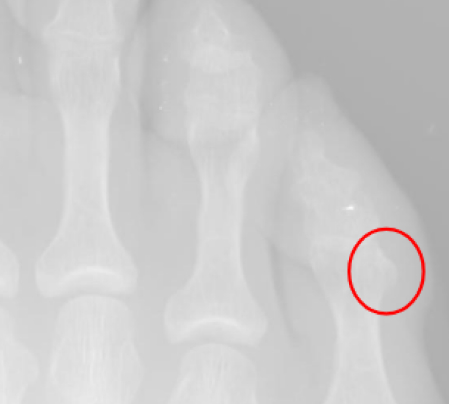

En las imágenes vemos osteofitos que en la piel generan un heloma dorsal del 5º dedo.